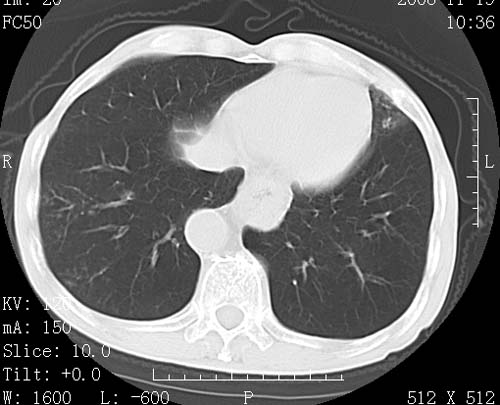

标题: CT16691:m 67 胃镜确诊食管下段及贲门癌 [打印本页]

标题: CT16691:m 67 胃镜确诊食管下段及贲门癌

术前查体,双肺部结节是转移?结核?请点评

转移 隆突下淋巴结亦肿大

首先考虑转移,纵隔内淋巴结亦肿大;

1)符合食管癌表现。2)两肺及纵隔淋巴结多发性转移瘤。3)左肺上叶舌段及两肺下叶炎症感染。

食管癌伴双肺转移,评述:肺部毛细血管网丰富,全身血液均快速流经肺部,癌细胞容易过滤定植,形成转移瘤,影象特点为以毛细血管末梢为中心的结节灶,边缘光滑锐利,少见有中心空洞着,不同来源的转移瘤可有各自特点,如甲状腺癌为双肺弥漫性微结节,本例有原发灶,双肺影象灶典型,左肺舌段条带状网格样伴胸膜天幕征,可视为癌性淋巴管炎。

左肺舌段有斑点钙化灶,能否说明是结核而不是转移?如果是转移将放弃手术改成化疗,如果是结核将考虑择期手术